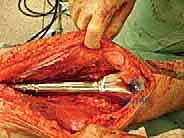

Exposure and Oncologic Resection

The incision is meticulously planned to incorporate the previous biopsy tract within an ellipse of skin, ensuring the tract is excised en bloc with the main tumor specimen to prevent local seeding. For a distal femoral resection, an extended anteromedial incision is utilized. Deep dissection proceeds through the virgin tissue planes, maintaining a thick cuff of normal muscle around the pseudocapsule of the tumor.

The neurovascular bundle (femoral/popliteal vessels) is identified proximally in the normal anatomy of the adductor canal and traced distally, carefully dissecting it away from the posterior aspect of the tumor block. Once the neurovascular structures are safeguarded and the joint capsule is appropriately addressed (often requiring intra-articular resection for distal femur, or extra-articular resection if the joint is contaminated), the level of the diaphyseal osteotomy is identified based on preoperative MRI measurements.

The osteotomy is performed using an oscillating saw under continuous saline irrigation to prevent thermal necrosis of the remaining bone. The entire tumor specimen is then delivered from the field and immediately sent for pathological evaluation of the margins.

A trial prosthesis is assembled and inserted. This is a critical step to assess limb length, joint line restoration, and soft tissue tension. The knee (or relevant joint) is put through a full range of motion. We assess for patellar tracking, varus/valgus stability, and ensure there is no impingement of the expansion mechanism. If the soft tissues are excessively tight, a slightly shorter modular segment may be required; if too lax, a longer segment is chosen to ensure joint stability.

Definitive Fixation and Soft Tissue Reconstruction

The final, and arguably most crucial, step for functional recovery is the soft tissue reconstruction. The extensor mechanism must be meticulously reapproximated. In cases where significant local muscle was resected to achieve oncologic margins, rotational muscle flaps (such as a medial gastrocnemius flap for the proximal tibia) are frequently employed to provide robust, vascularized soft tissue coverage over the metallic implant, drastically reducing the risk of postoperative wound breakdown and deep infection.